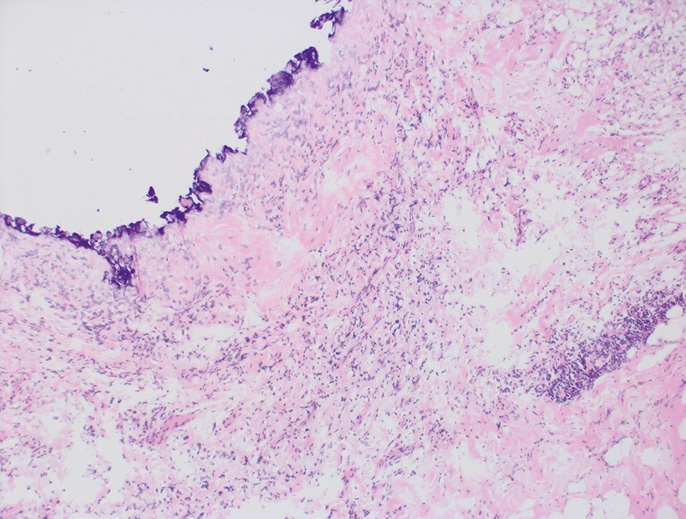

При обнаружении патологами окрашенных инвазивных клеток/рака in situ в фиксированном в формалине препарате (рис. 2) выполняли повторное хирургическое вмешательство (реиссечение соответствующего края резекции или мастэктомию, в том числе, с одномоментной реконструкцией). Все пациенты после ОСО независимо от характера хирургических краев подвергались послеоперационной дистанционной лучевой терапии.

Рис. 2. Плановое гистологическое исследование (ложе опухоли в крае резекции)

Fig. 2. Planned histological examination (tumor bed in the resection margin)